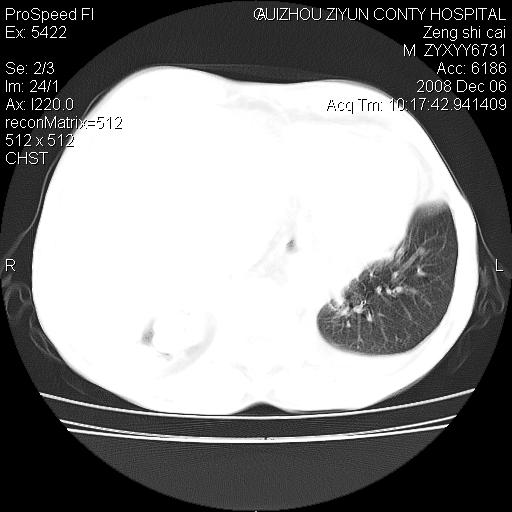

标题: CT16961:M、71岁,咳嗽半年,无血痰;胸片示右肺占位。 [打印本页]

标题: CT16961:M、71岁,咳嗽半年,无血痰;胸片示右肺占位。

1)考虑右肺上叶纵隔型肺癌伴纵隔淋巴结转移。2)心包积液,双侧胸腔积液。

右肺上叶纵隔型肺癌伴纵隔淋巴结转移。心包积液,双侧胸腔积液。